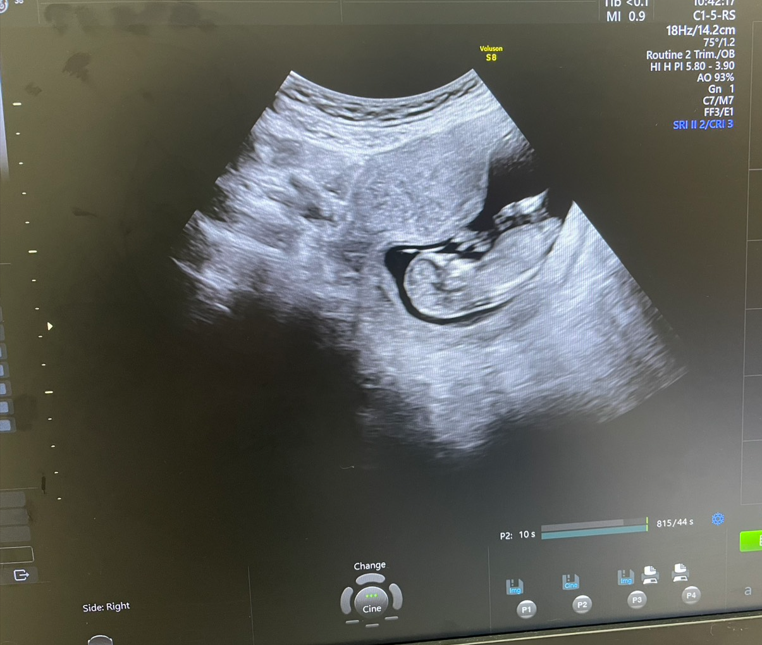

สวัสดีครับ ผมเป็นพ่อคนแล้วครับ

ผมอายุสี่สิบกลางๆ แฟนผมสามสิบกลางๆไม่แข็งแรงมีลูกยาก เคยหลุดไปรอบนึง 6-7 ปีที่แล้ว

หลังจากนั้นทำ IUI ไปสองรอบ ไม่ติดซักรอบ

ต้นปี ทำเรื่อง IVF ที่ รพ.จุฬา คิวยาวมากจนถึง กลางปีหน้า เลยถอดใจไปแล้ว ไม่มุ่ง ไม่คาดหวัง แต่มีไปมูไปขอตามที่แฟนอยากไป

รอบนี้มาเอง ผมทำเอง(ทำกับแฟน) ณ ตอนนี้ 15 Week แล้วครับ ได้ลูกสาว

ไม่มีอะไรมากแค่มาซุยมาขิงว่า ผมมีลูกคนแรกแล้วครับ